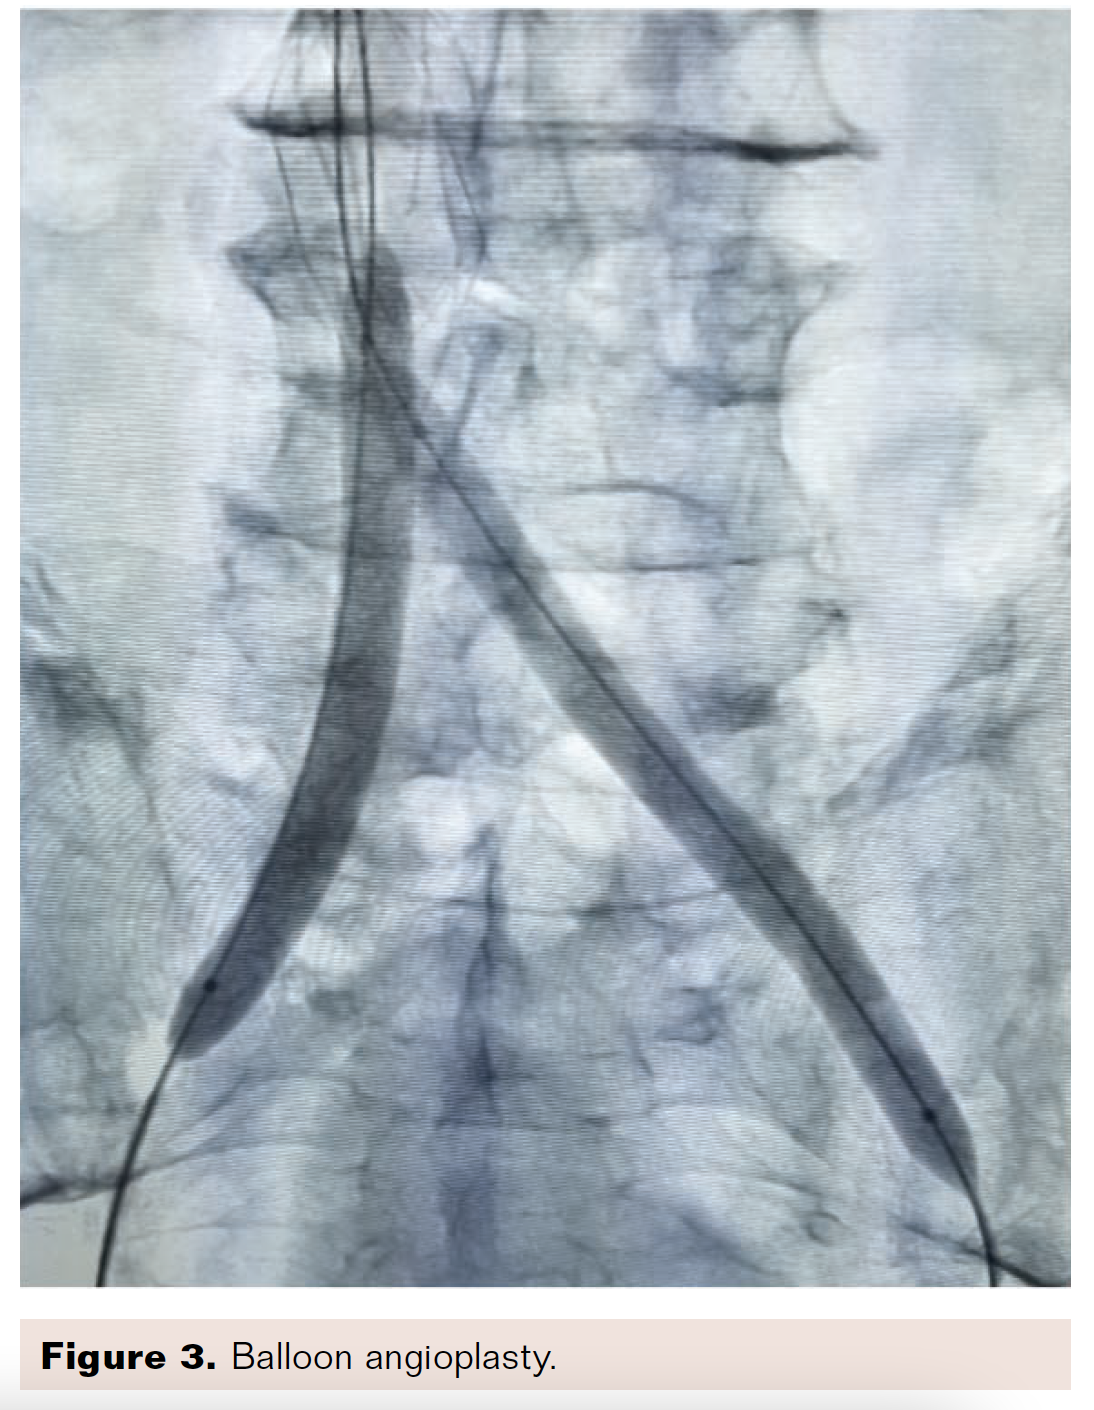

The vessels were diffusely diseased, making it difficult to establish a distal landing zone and reference vessel size. The hard, fibrotic plaque needed to yield before stenting, and the reference vessel size could not be adequately determined, so we decided to perform initial balloon angioplasty with undersized balloons at high pressure. Kissing balloon inflation through the IVC filter struts was performed with two 8 × 100 mm balloons at 20 atmospheres. These balloons were used sequentially to dilate the entire iliofemoral system (Figure 3). Following this dilation, we performed angioplasty in the bilateral iliac veins with 14 × 40 mm Atlas balloons (BD) with high pressure